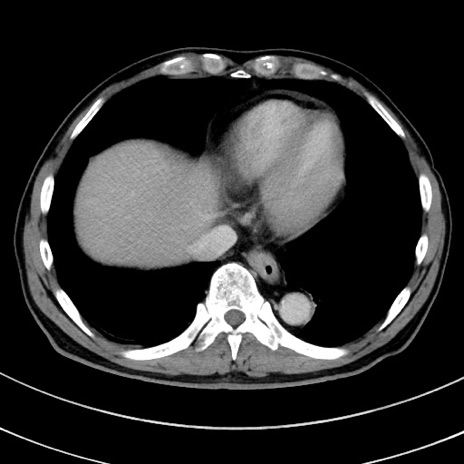

冠状断像